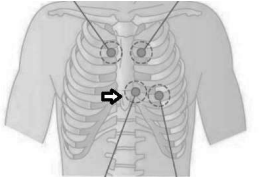

Na consulta de enfermagem, durante o exame

físico, o enfermeiro posiciona o estetoscópio no

ponto indicado pela seta na figura abaixo, qual foco

de ausculta está localizado neste ponto?